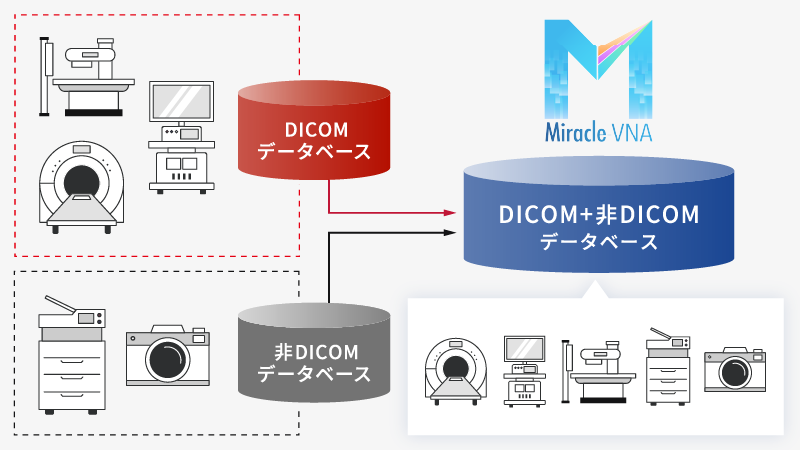

DICOM/非DICOMデータを一元管理

DICOM/非DICOMデータを一元管理

DICOMだけでなく、非DICOMデータや他の標準フォーマットもサポート。

異なるPACSやEMRシステムとシームレスに連携できる機能で、互換性を最大限確保します。